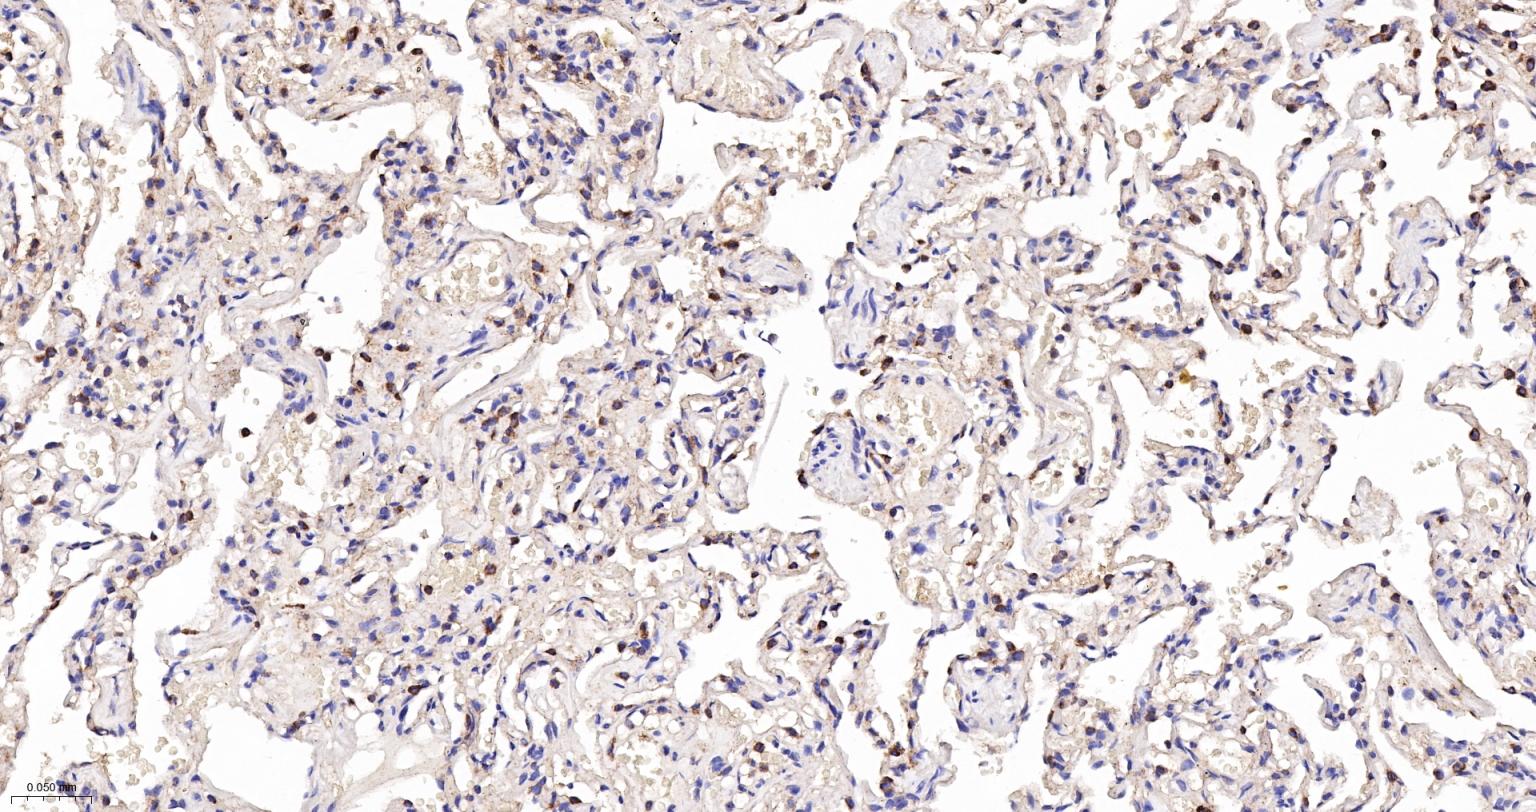

Paraformaldehyde-fixed, paraffin embedded Human Lung; Antigen retrieval by boiling in sodium citrate buffer (pH6.0) for 15 min; The section was incubated with EEF2 Monoclonal Antibody, Unconjugated (bsm-61650R) at 1:200 overnight at 4°C, followed by conjugation to the bs-0295G-HRP and DAB (C-0010) staining.